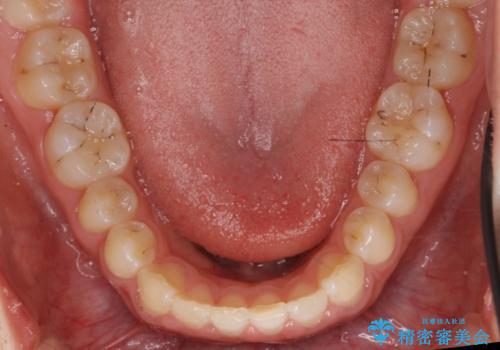

前歯のすきま 矯正治療とセラミックで小さな歯を形良く

- 前歯のすきまを気にして来院。

左上の2番が生まれつき小さく、スペースが余っていました。

右上の2番もやや小さめでしたが、相談の上、左上2番のみセラミックで形を整えることとしました。

そのほかの隙間はマウスピース矯正で閉じることにしました。

- 総額99万円 (矯正治療:85万円 左上2:ジルコニアクラウン スペシャル 13万円、仮歯 1万円)費用は治療当時の料金となります